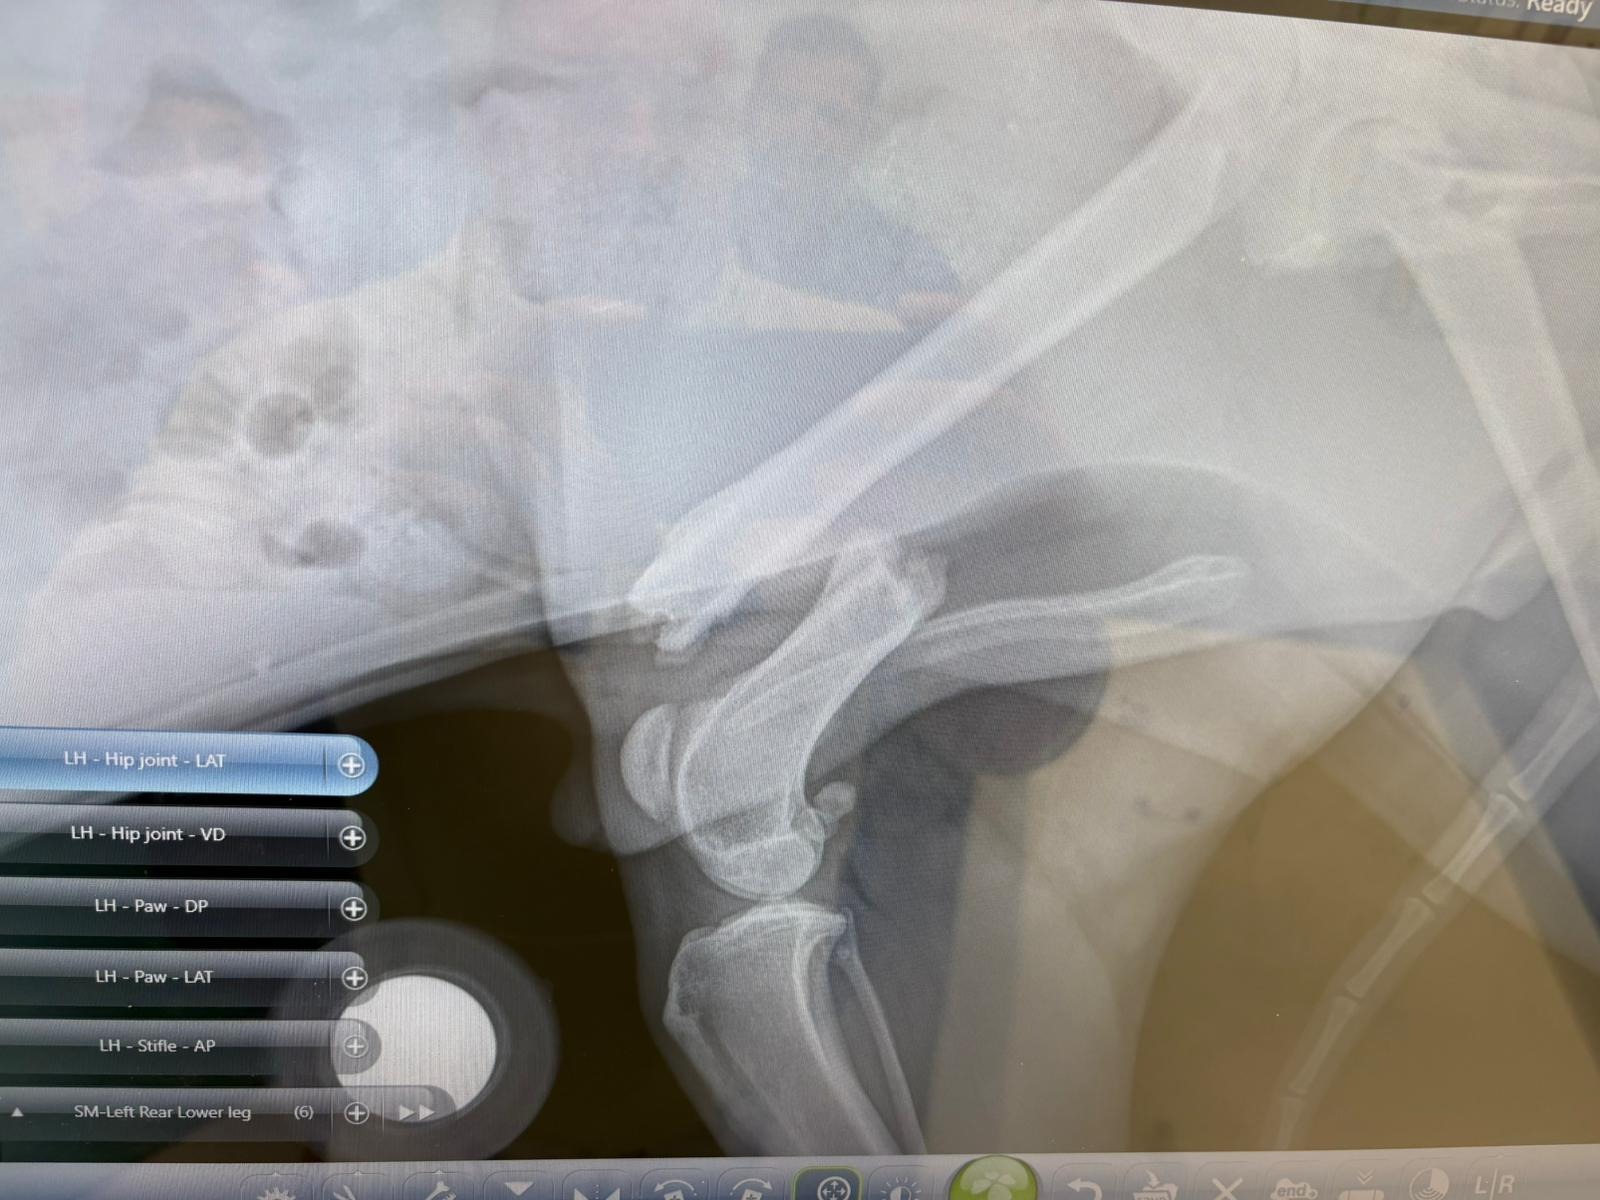

He was found as a starving street dog in the small town of Progreso, Yucatan, Mexico, alone, suffering, and unable to walk. His right back femur was broken, and without help, he would have died—slowly and painfully from starvation.

He was rescued just in time and brought to a local vet, where his leg was set. Sadly, it didn’t heal properly. Despite everything, Bruno remained what he is at his core: gentle, trusting, and full of love.

But shortly after arriving, the unthinkable happened—his leg broke again.

They made the decision to give him the best possible outcome—a complex orthopedic surgery costing $5,300.